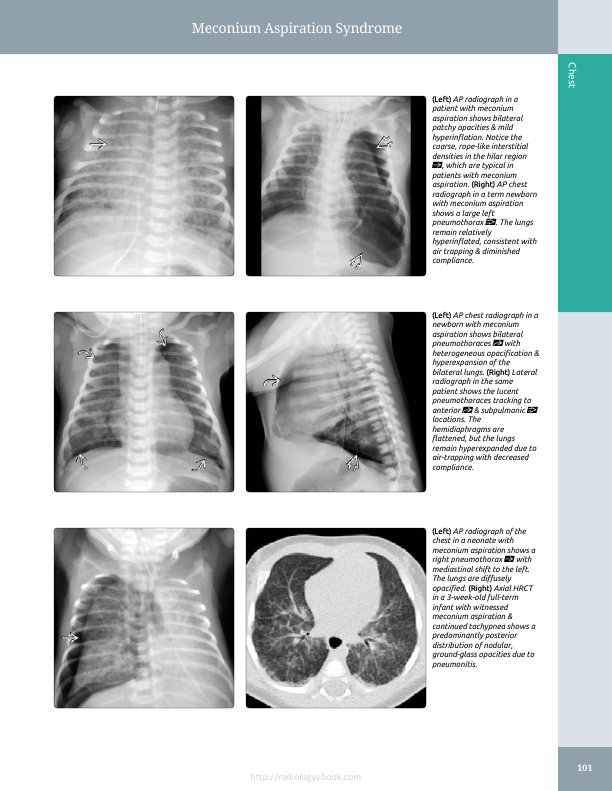

Представлена рентгенограмма ОГК новорожденного. Можно было бы голову сломать на тему "Что это?", если бы не направление "Аспирационный синдром". Еще раз о приоритете  клиники перед рентгеновской картиной в диагностике неонатальных ОГК. Речь идет о диагностике НЕ аспирации (есть или нет аспирация, ставится, в основном, клинически), а диагностике выраженности изменений в легких при аспирации.